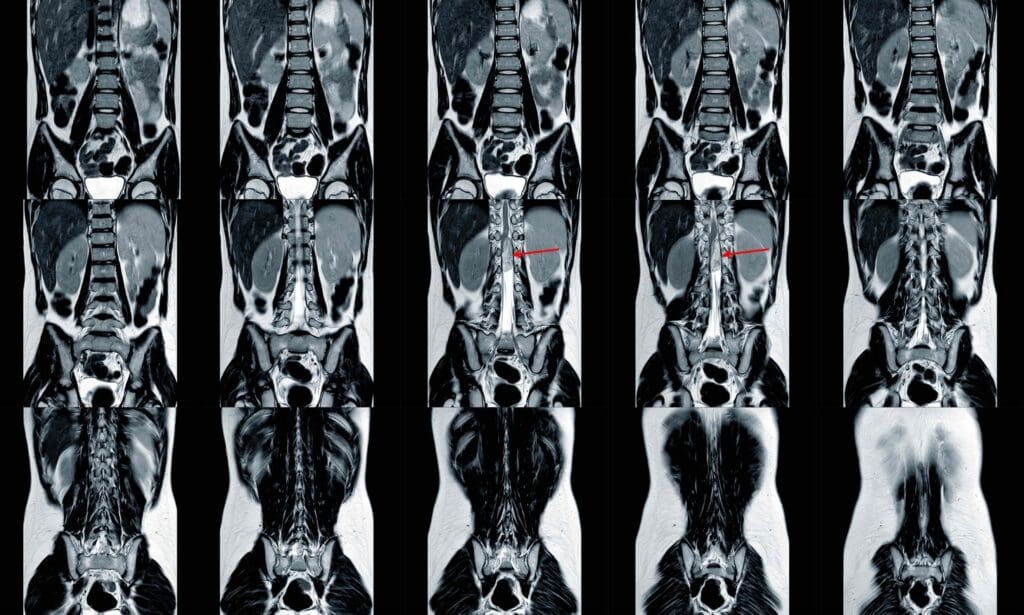

A detailed x-ray image of metastatic bone cancer, showing multiple lesions and osteolytic destruction throughout the skeletal structure

Bone metastases happen when cancer cells move from another part of the body to the bones. This creates secondary bone cancer. The process is complex, involving several steps. First, cancer cells detach from the main tumor. Then, they enter the bloodstream and settle in the bones.

Imaging Technologies: X-rays, CT, MRI, and Bone Scans

Imaging is key in spotting bone metastases. We use different tools to see how much of the bone is affected.

• X-rays: Good for finding big bone problems and breaks.

• CT (Computed Tomography) scans: Show detailed bone pictures and find small issues.

• MRI (Magnetic Resonance Imaging): Very good at finding bone marrow and soft tissue problems.

• Bone scans: Use a tiny bit of radioactive stuff to show active bone areas, which might have metastases.